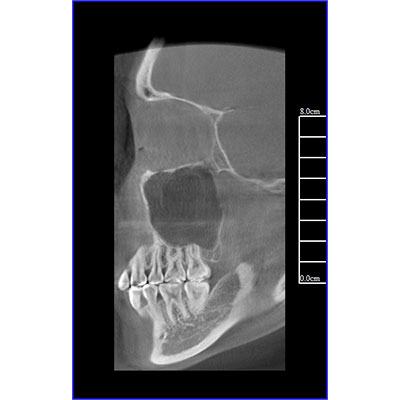

该款牙科CBCT产品采用动态平板探测器,获得三维图像的同时还具有数字化全景功能,广泛应用于口腔颌面外科、正畸科、正颌外科、种植科、牙体科、颞下颌关节科等术前术后。

三维重建任意断层

专有三维重建算法,可提供任意位置高清断层影像。

多平面组合重建

可同时观察轴向面、冠状面和矢状面图像,方便临床诊断。

Clinical picture

临床图片